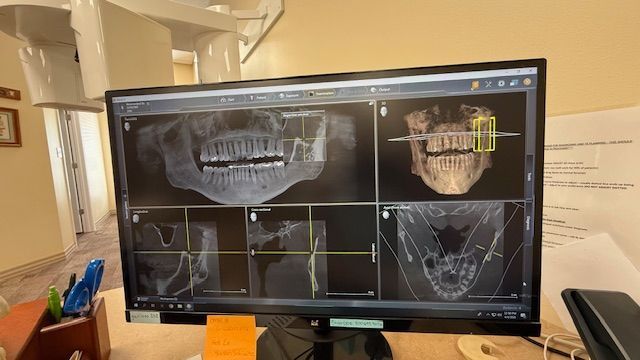

At our office, we’re proud to be one of the only dental practices in the region equipped with advanced Panoramic and Cone-Beam Computerized Tomography (CBCT) technology. Think of it like an MRI for your head, neck, and mouth—this powerful tool gives us detailed 3D images from multiple angles and “slices,” allowing us to detect issues, identify pathology, and deliver far more accurate diagnoses than traditional imaging. It’s just one of the ways we’re committed to providing the highest level of care.

- Comprehensive Diagnosis: A panoramic x-ray provides a detailed and complete view of your teeth, jaw, and surrounding areas, allowing us to identify conditions that may be missed with traditional x-rays.

- Early Detection: By providing a full view of the head and neck area, panoramic x-rays help us detect issues such as tumors, cysts, bone loss, impacted teeth, and other conditions that could affect your oral health.

- Better Treatment Planning: The comprehensive images from a panoramic x-ray help us plan treatments with greater accuracy, whether you're undergoing a routine checkup, orthodontic evaluation, or preparing for dental surgery.